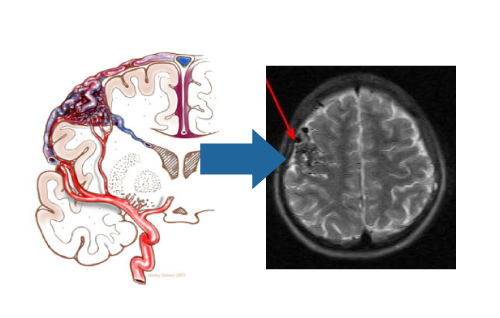

脳動静脈奇形は流入動脈>ナイダス(本体)>導出静脈と3つのコンポーネントから出来ており、ナイダスより導出静脈への移行部が最も脆弱となっています。また、同部が本病態の主体箇所となっております。

脳動静脈奇形に対するガンマナイフ治療計画(図1)

(各球状照射野を腫瘍のみに配置し、脳への過照射を避ける)